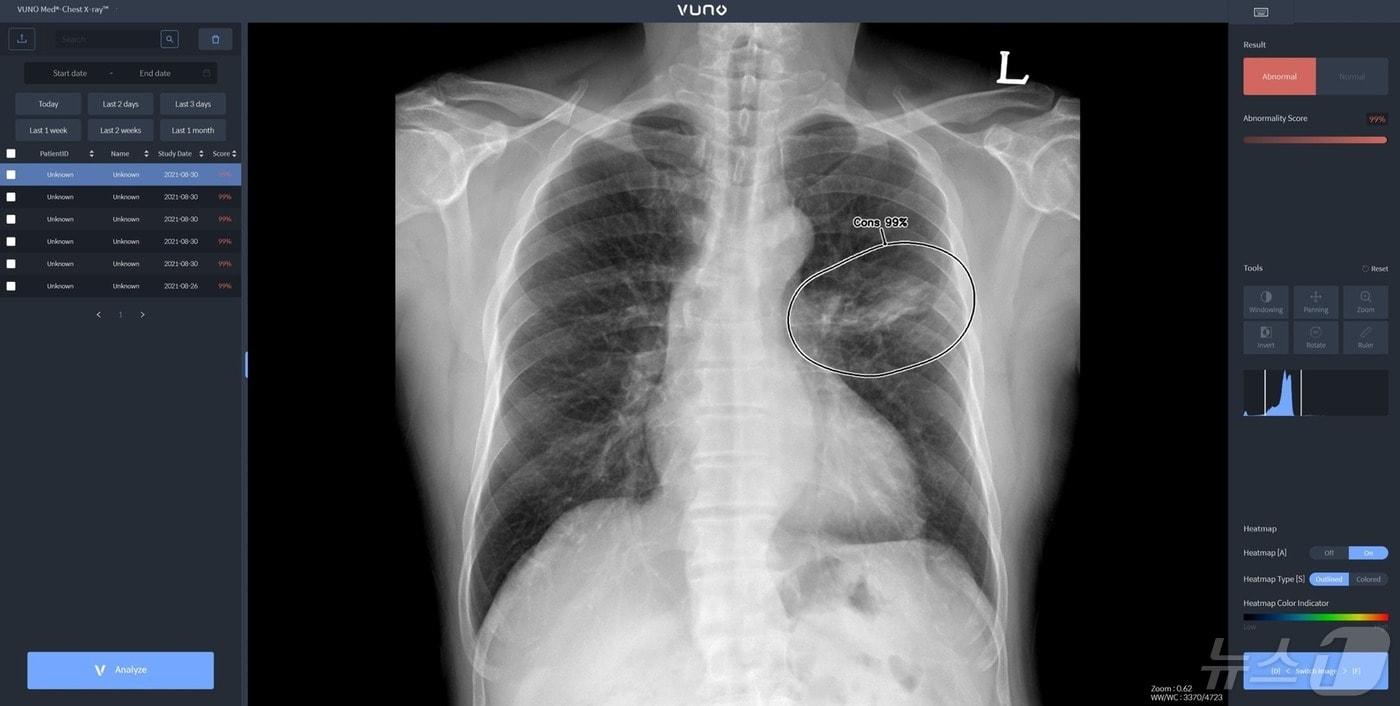

본문 이미지 - 뷰노메드 체스트 엑스레이 활용 모습.(뷰노 제공)/뉴스1 ⓒ News1

뷰노메드 체스트 엑스레이 활용 모습.(뷰노 제공)/뉴스1 ⓒ News1